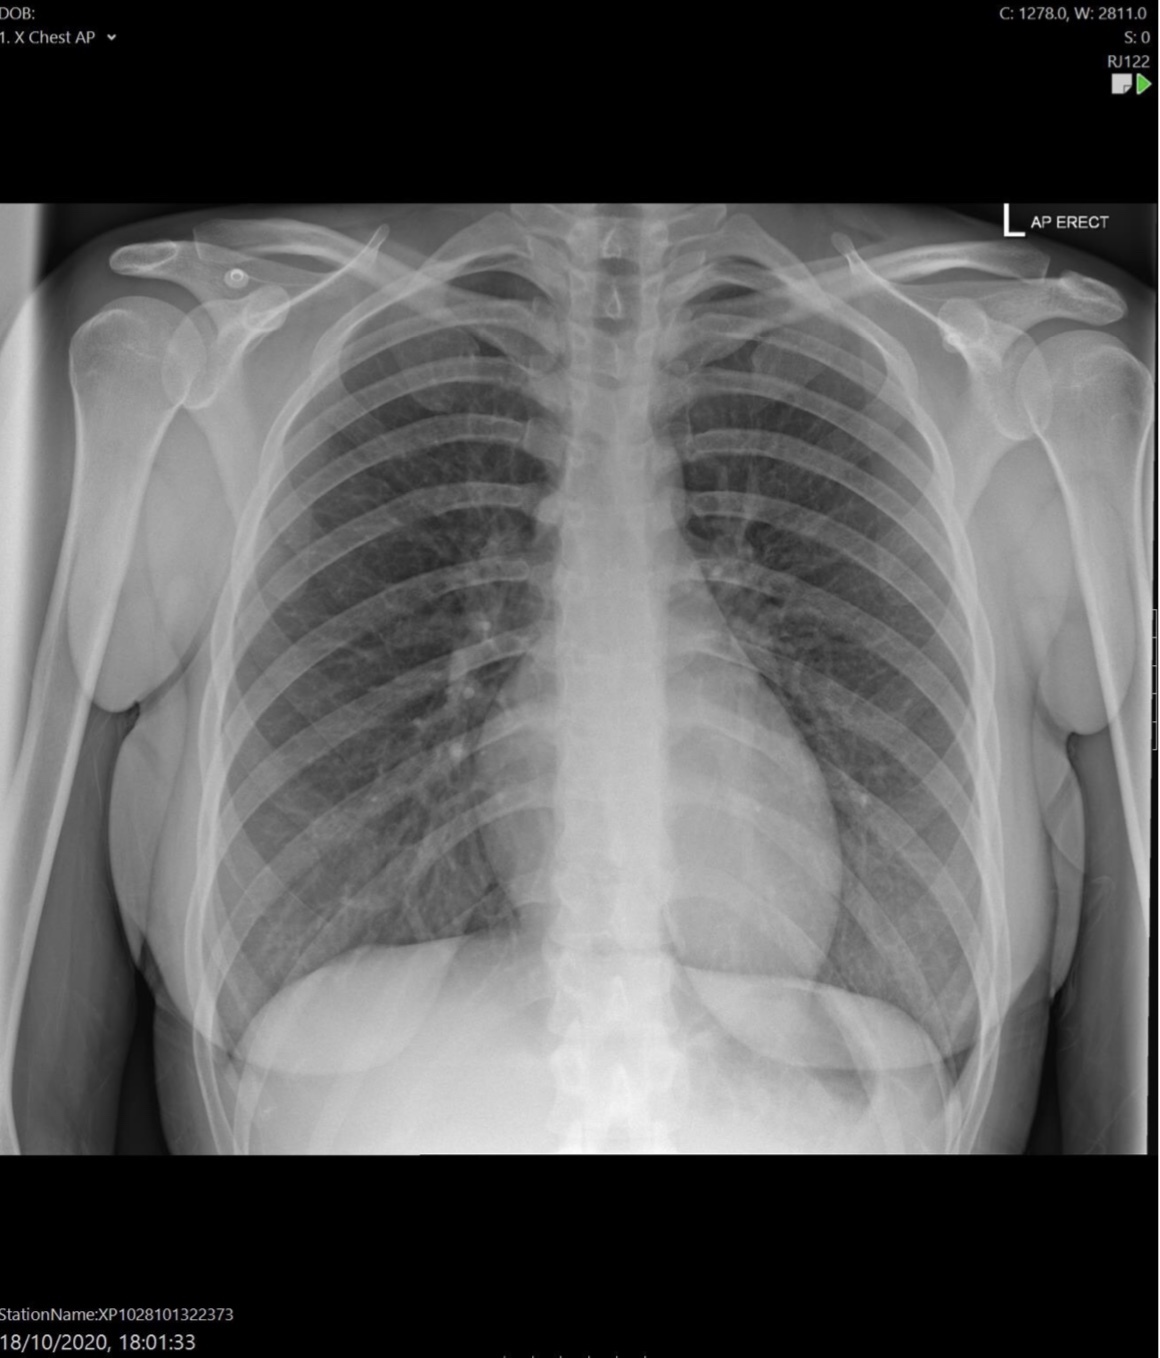

What is the disadvantage of an AP CXR?

It makes the heart look larger

Cardiomegaly (although AP so can’t assess properly)

Dilated upper lobe vessels

Pleuarl effusion